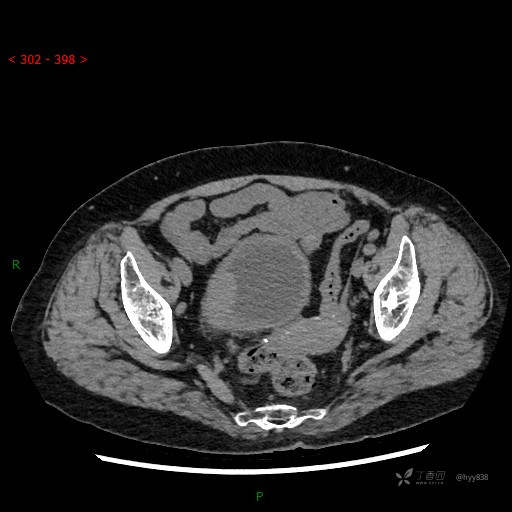

膀胱CT平扫(2022.10.20)